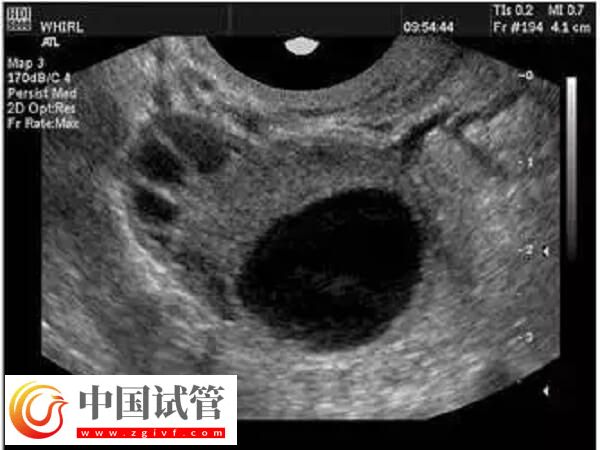

正常情況下,女性每個月只會有一個成熟的卵子形成并排出,然后和精子進行結(jié)合。試管嬰兒為了進一步提高成功率,往往都會經(jīng)歷促排卵階段,促使女性卵巢中的多個卵泡同時發(fā)育成熟,然后進行取卵,取卵的數(shù)量和質(zhì)量關(guān)系到試管的成功率。下面給大家分析一下取卵出現(xiàn)異形卵子的原因: